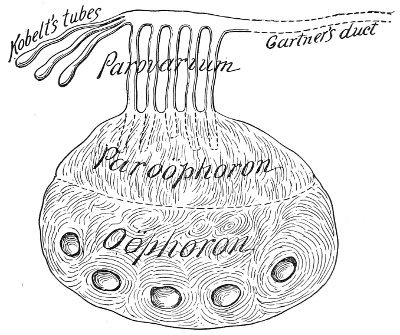

The origin of vaginal cysts has been much disputed. It is probable that they arise from the remains of the Wolffian canal—the canal of Gärtner. In the embryo the transverse or longitudinal tubule of the parovarium extends to the side of the uterus and thence down the side of the vagina to the urethral orifice. It persists in this condition in some of the lower animals—the sow and the cow—and may also persist as a closed tube in woman. In such cases it may become distended and form the vaginal cyst.